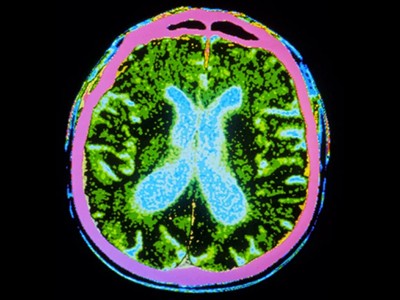

截至去年12月,共有83種源自多能干細胞的產品正在進行115項臨床試驗。帕金森病的治療方法比任何其他中樞神經系統疾病的治療方法都處于更先進的發展階段。帕金森病的特征是釋放神經遞質分子多巴胺的神經元逐漸喪失。帕金森病相關的運動癥狀,例如肌肉僵硬、運動遲緩、震顫和步態障礙,都是由中腦黑質區域神經元的耗竭引起的。

這種方法開創于20世紀80年代:研究人員從胎兒腹側中腦(被認為富含多巴胺能神經元)中提取細胞,并將其移植到帕金森病患者的紋狀體(中腦神經元向其發送投射的區域)中。后續研究表明,移植區域的多巴胺含量恢復正常,運動功能得到改善,并且這種效果在移植后持續多年。

帕金森病是由于大腦中釋放多巴胺(多巴胺能)神經元逐漸喪失所致。Sawamoto 等人1和 Tabar 等人2進行了一項基于干細胞治療的臨床試驗。兩個團隊都使用了臨床級多能干細胞來補充多巴胺能神經元,這種細胞可以無限分裂并分化為任何細胞類型。Sawamoto等人使用了源自健康成年捐贈者細胞的誘導多能干細胞系,而Tabar等人使用了源自早期胚胎的人類胚胎干細胞系。干細胞經過培養,形成多巴胺能神經元祖細胞。這些細胞被移植到稱為殼核的大腦區域,殼核與尾狀核一起形成紋狀體。紋狀體與黑質相連,而黑質是多巴胺能神經元損失最為嚴重的部位。早期(I/II期)臨床試驗主要證實了該療法的安全性,同時也表明其在改善癥狀方面具有一定有效性。